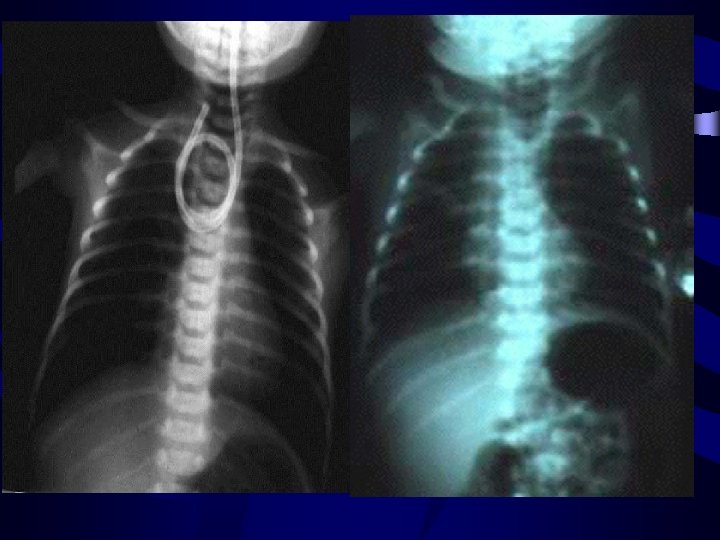

RADIOLOGIE • La radiographie thoraco-abdominale de face et cliché cervicothoraciquede profil; sonde opaque en place. • permet de voir le cul de sac oesophagien supérieur et détermine le type d’atrésie selon l’aération d’aval et les éventuelles anomalies associées (vertèbres squelette , silhouette cardiaque).

• L’oesophagographie est rarement necessaire • Injection d’air dessine parfaitement le cul de sac superieur

RADIOLOGIE • Cliché thoraco-abdominal de face et de profil; sonde en place: • Présence de clartés de type intestinal en intrathoracique • Abdomen désertique de clarté • Déviation du médiastin